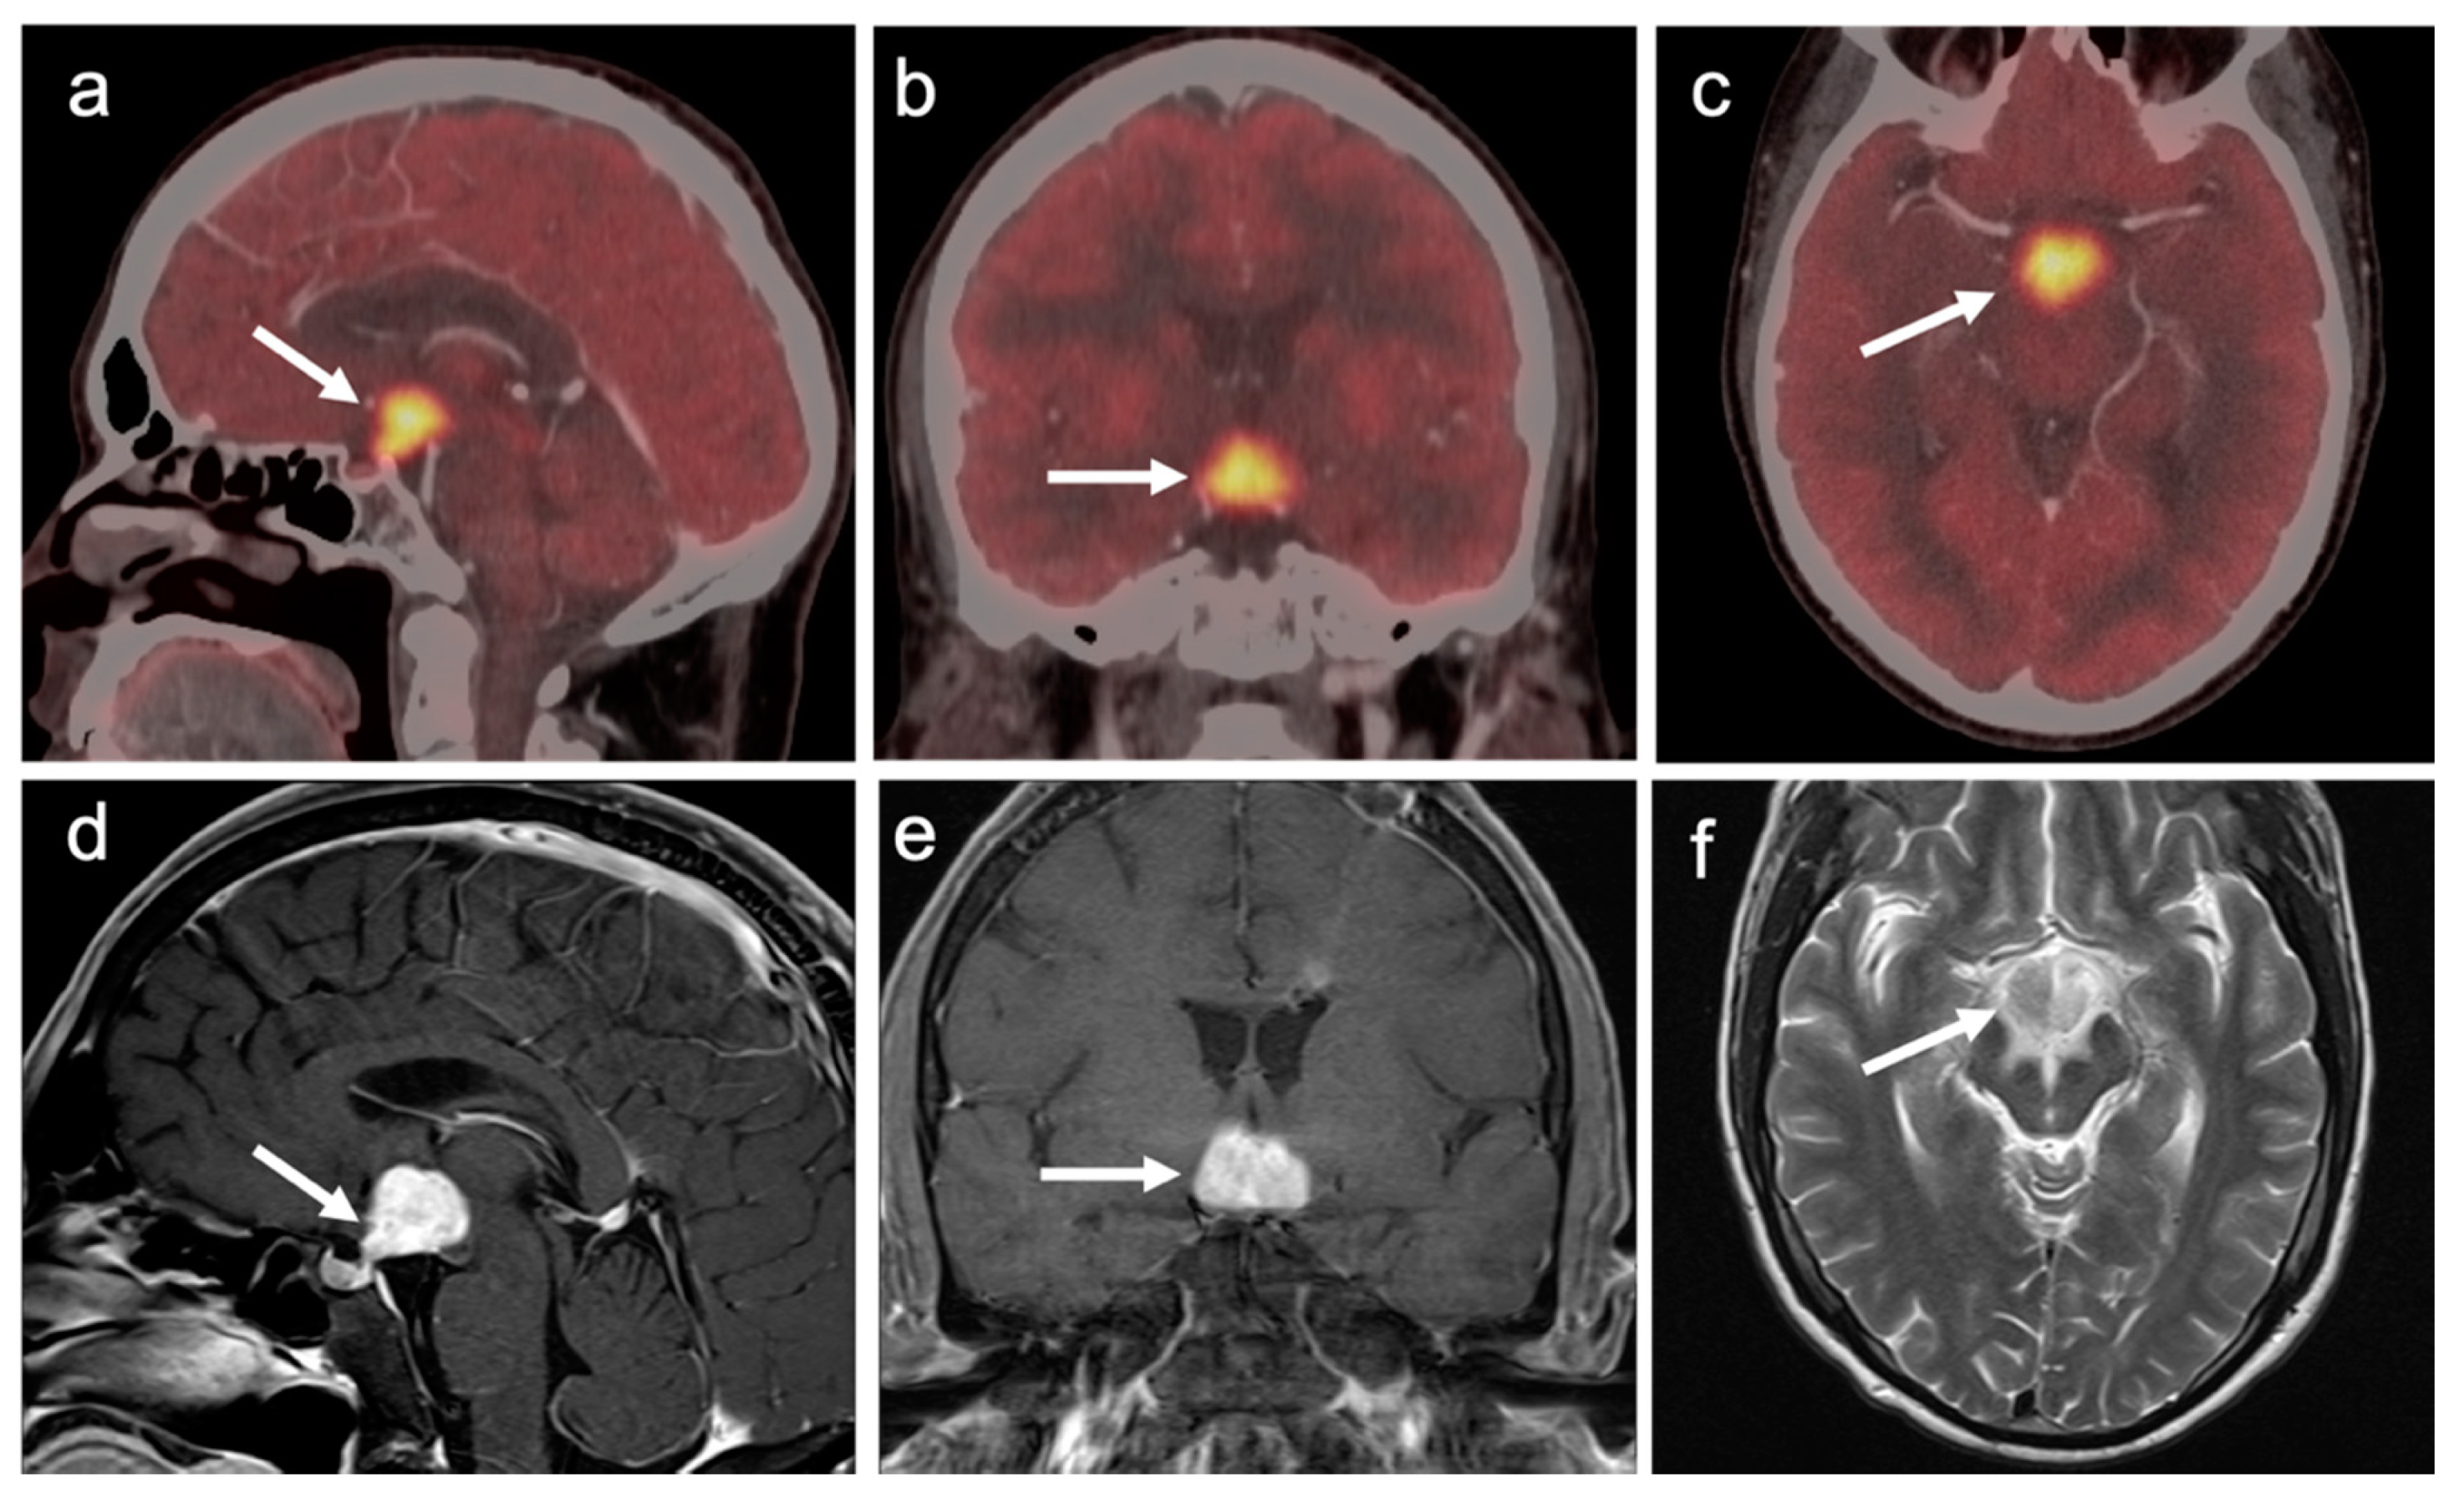

3.7. Meningioma